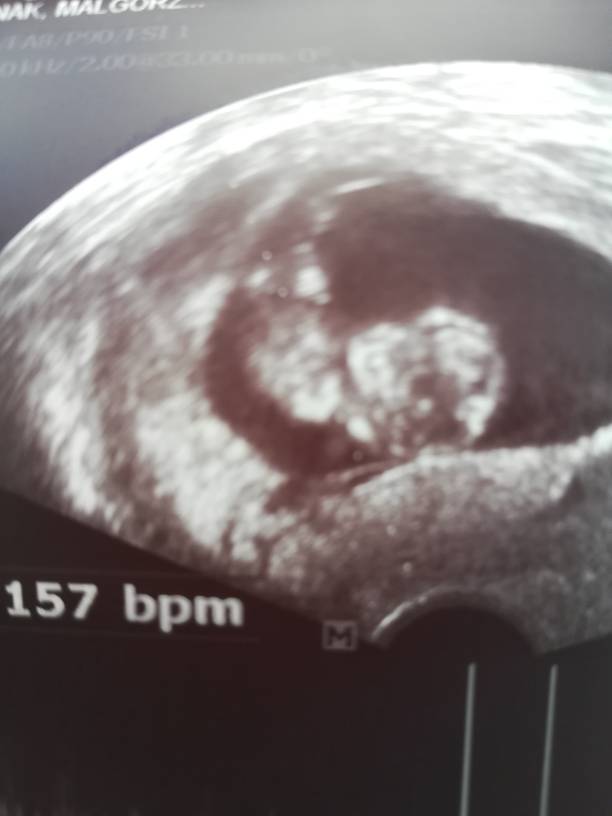

Który to tydz? Śliczne maleństwoJuż po wizycie, maleństwo ma 4,17 cm, serducho bije 157 razy na minutę[emoji7][emoji7][emoji7]Zobacz załącznik 871098

Suuuper, ktory tc? Brawo, piekna dzidzia [emoji4]Już po wizycie, maleństwo ma 4,17 cm, serducho bije 157 razy na minutę[emoji7][emoji7][emoji7]Zobacz załącznik 871098